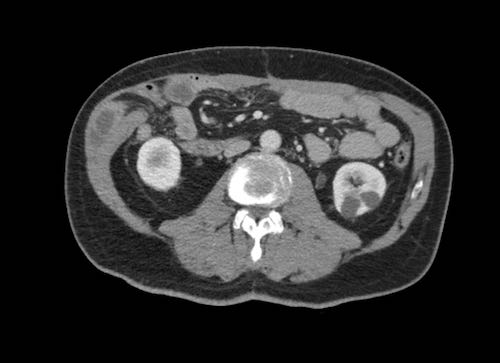

Ca lâm sàng 2

Cuộn qua các lát cắt.

Bạn có thể phát hiện tất cả các tổn thương cấy ghép phúc mạc không?

.jpeg)